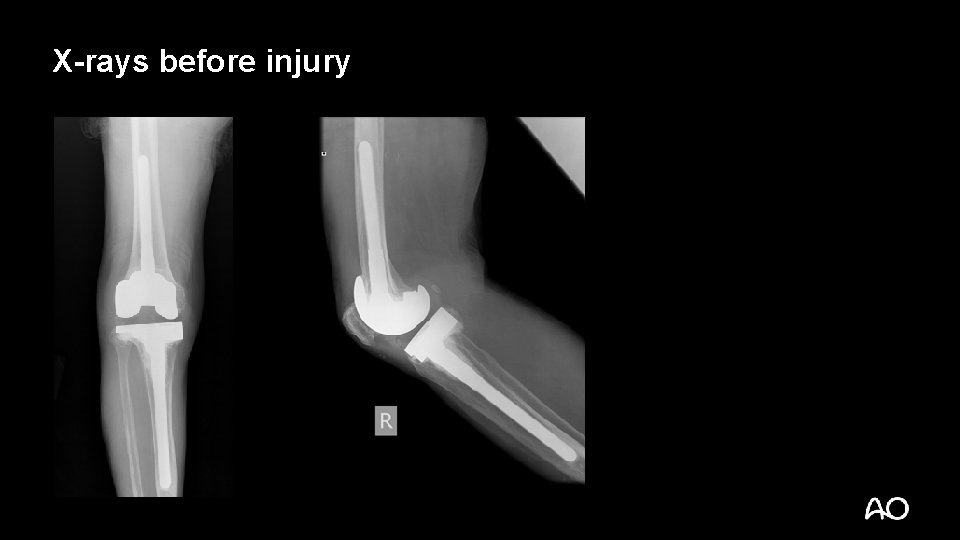

Case description • • • 75 -year-old woman Bilateral OA knees, TKA 13 years ago Right revision TKR 8 years previous Known HIV+ for 20 years, on long-term anti-HIV treatment Walks with a stick Complained of thigh pain after a fall on level ground

X-rays before injury